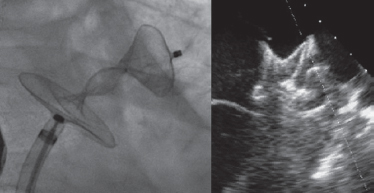

A 28-mm Amulet device was chosen to perform the procedure. A 14-Fr introducer sheath was advanced into the left atrium and, after a selective angiography, the device was deployed inside the LAA in a regular fashion. The first deployment did not achieve a good position (partially outside the appendage) and the device had to be recaptured. A second attempt was made with significant counterclockwise rotation of the sheath that achieved a peculiar “twisted” deployment of the body of the device (figure 2) whose distal part was actually deployed inside the appendage. It was carefully recaptured and after discarding pericardial effusion, it was re-implanted in a good position this time with no further need to change the device (figure 3). A transthoracic echocardiography performed the next day revealed no pericardial effusion. The TEE performed 1 month later revealed no leaks or thrombi on the device either.

Figure 2.